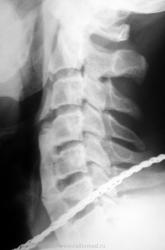

Абсолютно согласен с Nela, болезнь Форестье, крайняя степень проявления. А с С6, по моему, все в порядке, похоже просто артефакт создает видимость дефекта. Хотя по одному снимку тяжело. Но по логике - на фоне таких костных масивов -дефект будет нонсенсом......

Коллега STOVBAV! Боюсь, мы не совсем понимаем друг друга.Вы считаете, что это б.Ф.? Да, рентгенологически - один в один. Но б.Ф. - это болезнь старческого возраста. Здесь - далеко не старик. И я думаю, что травма явилась пусковым моментом для такого массивного обезыствления перед. прод. связки.Обратили внимание на отсутствие обезыствления на уровне ПДС CIII-CIV? Голова больного ведь крутится. При б.Ф. такого разрыва не было-бы. А в остальном - б.Ф. один в один. Поэтому я это трактую как реакция связок, организма ТИПА б.Ф.

Здравствуйте! Опять скажу честно, всех обстоятельств случая не помню, не судите... Но посчитал возможным представить этот единственный интересный снимок Вашему вниманию. То, что наблюдение вызвало оживленное обсуждение - это подтверждает. Моя оценка снимка немного в другой плоскости - никто не указывает на наличие вероятно старых, но отчетливо видимых на снимке поперечных переломов данного обызвествления, какой бы природы оно не было... А ведь именно эти переломы могут доставлять больному страдания не меньшие чем основной процесс. Переломы - их линии отчетливо видны на уровне дисков рядом с С6. А если не переломы то что?

Болезнь Форестье - фиксирующий лигаментоз? Только не пойму куда делась часть тела 6 позвонка!

обызвествление всего превертебрального пространства, похоже на оссифицированную гематому

Прямо, создается впечатление подсвязочного костеобразования.

Нет, именно для б.Форестье. При Б.Б. спина прямая как палка, может быть сутулость. Кстати, коллега GONCHAROVA... высказалась в пользу обезыствления подсвязочной гематомы. Я с ней полностью согласен.